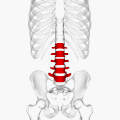

![]() Position of human lumbar vertebrae (shown in red). It consists of 5 bones, from the top down, L1, L2, L3, L4 and L5. | |

The lumbar vertebrae are located between the thoracic vertebrae and pelvis. They form the lower part of the back in humans, and the tail end of the back in quadrupeds. In humans, there are five lumbar vertebrae. The term is used to describe the anatomy of humans and quadrupeds, such as horses, pigs, or cattle. These bones are found in particular cuts of meat, including tenderloin or sirloin steak.

In human anatomy, the five vertebrae are between the rib cage and the pelvis. They are the largest segments of the vertebral column and are characterized by the absence of the foramen transversarium within the transverse process (since it is only found in the cervical region) and by the absence of facets on the sides of the body (as found only in the thoracic region). They are designated L1 to L5, starting at the top. The lumbar vertebrae help support the weight of the body, and permit movement.